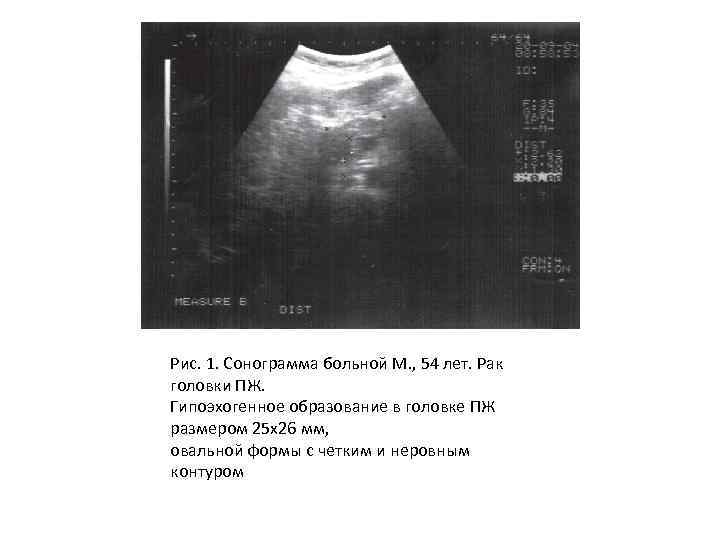

Рис. 1. Сонограмма больной М. , 54 лет. Рак головки ПЖ. Гипоэхогенное образование в головке ПЖ размером 25 х26 мм, овальной формы с четким и неровным контуром